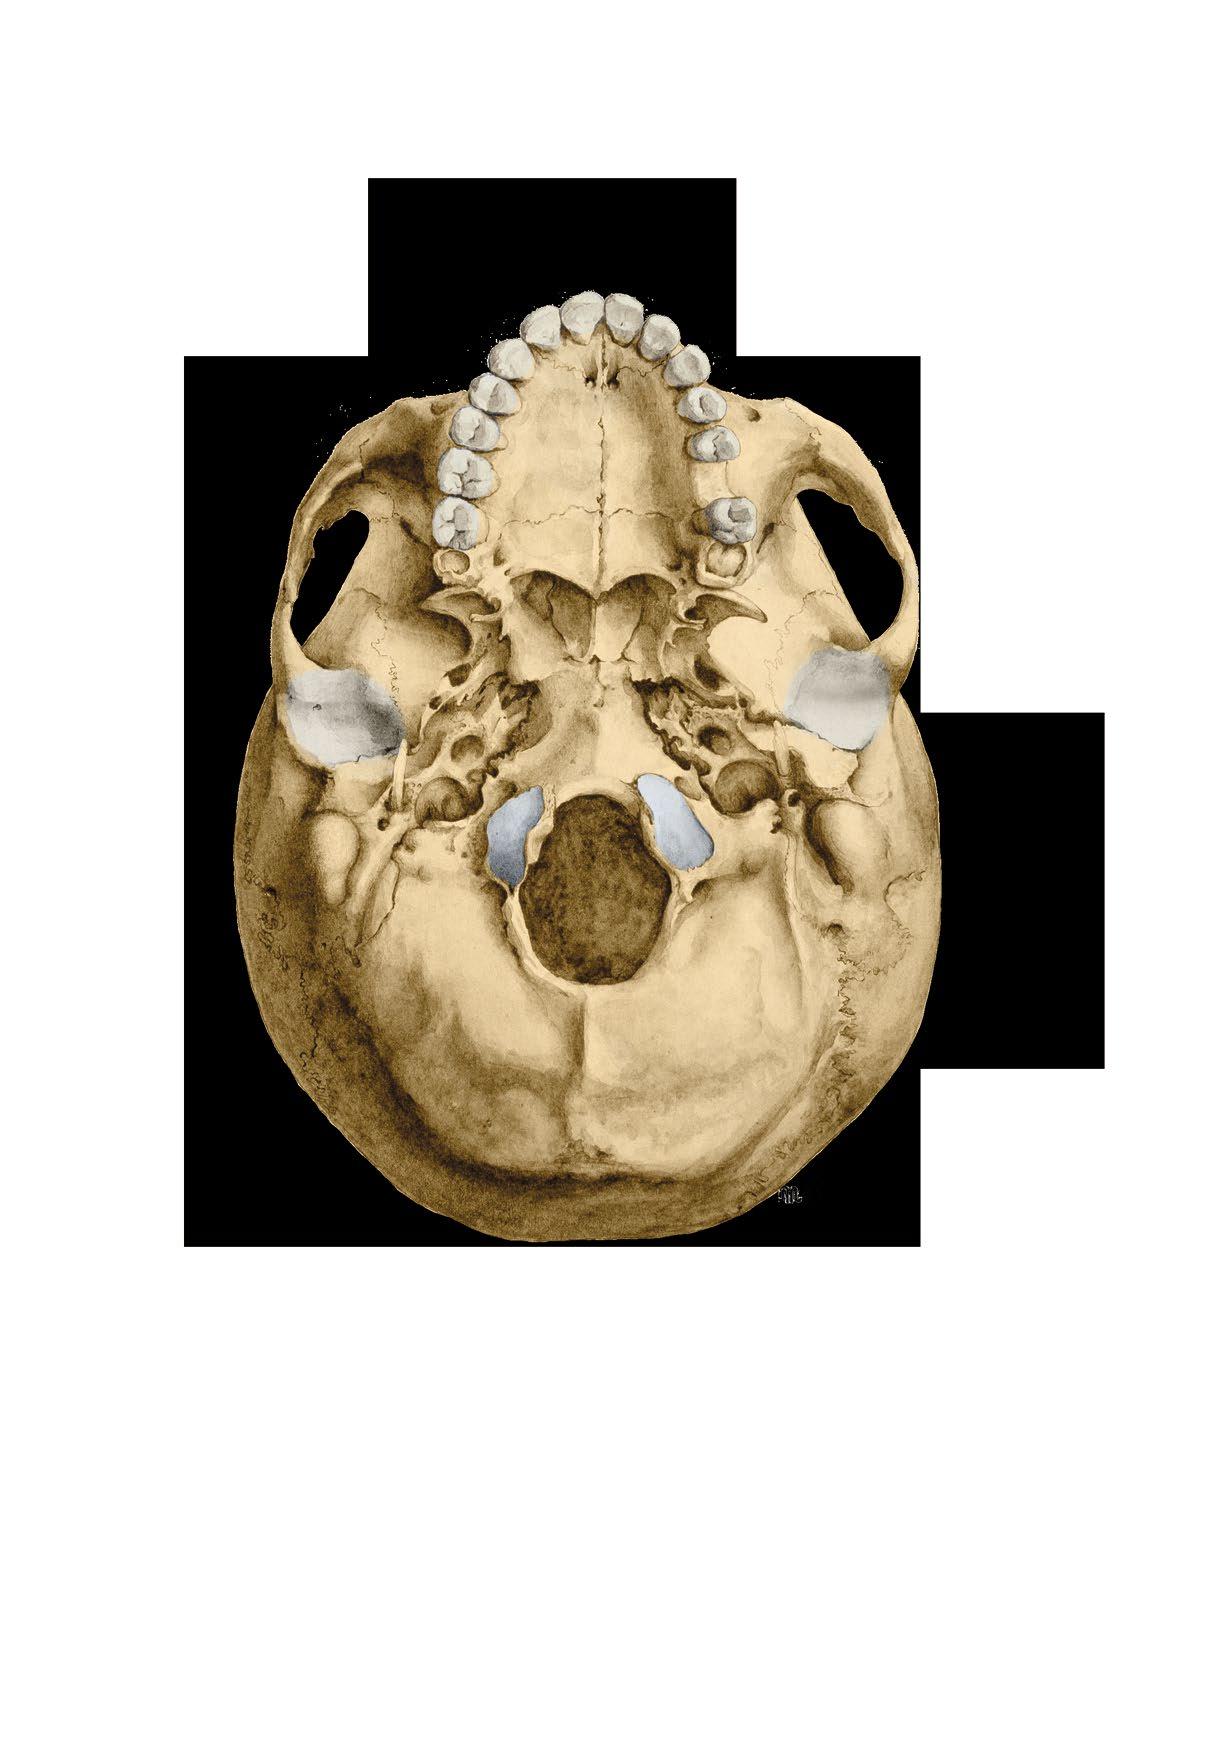

Basis cranii externa et interna

a zevní plocha base lební

b vnitřní plocha base lební

c členění vnitřní plochy base

fossa cranii posterior

External and internal base of the skull

a external surface

b internal surface c cranial fossae

Basis cranii externa, zevní plocha spodiny lebeční

foramen incisivum

foramen infraorbitale

arcus zygomaticus

lamina lateralis processus pterygoidei

foramen lacerum

fossa mandibularis

porus acusticus externus

foramen stylomastoideum

sulcus arteriae occipitalis

foramen mastoideum

canalis condylaris

planum nuchale

protuberantia occipitalis externa

External surface of the base of the skull